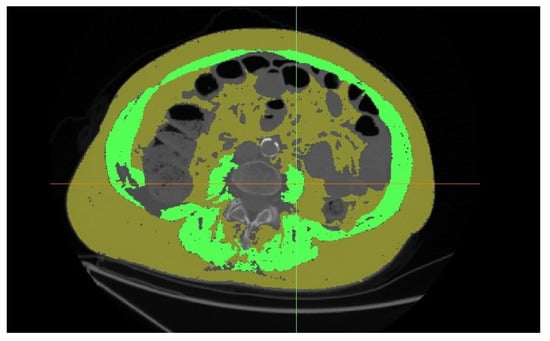

| Median sarcopenic obesity (IQR) (cm2/cm2) | 2.30 (1.33–3.19) | 2.29 (1.23–3.10) | 2.50 (1.62–3.84) | 0.093 |

| Number of patients with sarcopenic obesity under cut-off point | 31 (11.9%) | 20 (9.3%) | 11 (24.4%) | 0.004 |